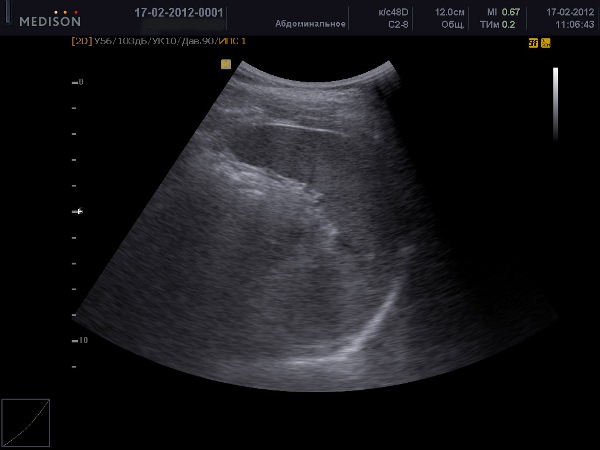

Пациенты проходят УЗИ селезенки, находясь в положении лежа на спине. Сначала проводятся параллельные срезы, затем специалист перемещает датчик от реберной дуги до нижнего полюса органа. После этого пациента просят перевернуться на правый бок, чтобы провести более детальное сканирование, вращая датчик для получения поперечных срезов. Если в процессе исследования не обнаруживаются предполагаемые отклонения, пациента просят перевернуться на живот и УЗИ продолжается.

После проведения УЗИ селезенки следует интерпретация результатов. Нормальная и здоровая селезенка должна находиться в верхней части брюшной полости, слева, ниже диафрагмы. Желудок должен быть расположен близко к середине органа, а хвост поджелудочной железы должен находиться в середине ворот. Наличие сосудистой сетки в зоне ворот не является отклонением. Диаметр селезеночной вены не должен превышать полсантиметра. Здоровая селезенка имеет однородную мелкозернистую структуру паренхимы.

Важными являются не только размеры селезенки, но и ее эхоструктура, которая должна быть однородной. На изображении не должно быть никаких вкраплений. В норме форма селезенки напоминает полумесяц. Если структура органа неоднородная (что свидетельствует о наличии доброкачественных опухолей), эхогенность повышена (при онкологических заболеваниях крови она может быть нормальной, но может быть отмечена спленомегалия) и форма селезенки неправильная, это указывает на наличие заболевания. Даже незначительные отклонения от стандартных показателей имеют значение и требуют консультации специалиста.